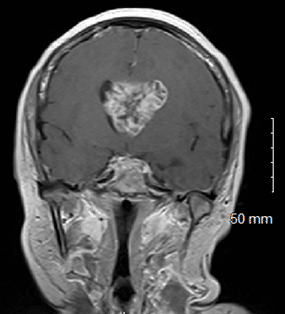

Lateral Intraventricular Glioblastoma Presentation with Increased Survival Rate

Background: Although glioblastoma is the most common malignant primary brain tumor, it rarely presents in the intraventricular region(s) of the...Read More